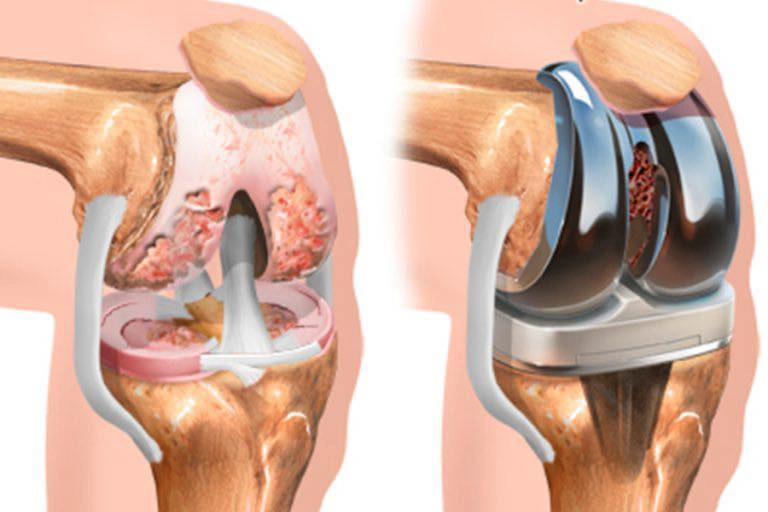

Prótesis de rodilla

Al ser la cirugía protésica más habitual en España, veamos en qué consiste una cirugía protésica de rodilla. Normalmente esta intervención se indica en pacientes que sufren de artrosis en la articulación y con dolor constante. Además de la deformidad de la articulación y los problemas de movilidad, causados por estos, todo ello le impide volver a su vida cotidiana limitando sus actividades habituales, siendo muy relevantes los casos graves en que llegan a despertarse en mitad de la noche o no pueden conciliar el sueño por causa del dolor.

La prótesis unicompartimental, en lugar de sustituir la totalidad de la articulación, sustituye solo una parte, que puede ser la parte interna (medial), la parte externa (lateral) o la parte de la rótula de la rodilla. Lo más frecuente es utilizarla en la zona medial.

Con este tipo de prótesis, se extrae tan solo la parte de la rodilla que se encuentra deteriorada y se coloca una articulación artificial para devolver movilidad y estabilidad tan solo a la zona afectada. El resto de estructuras de la articulación quedan intactas y en el estado anterior a la operación, aunque toda la articulación se beneficia de esta intervención.